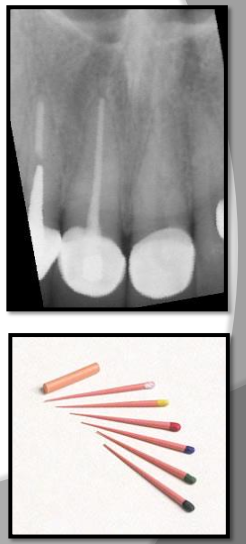

What are Gutta percha?

Gutta percha - clay-like thermoplastic material used in root canal therapy to obliterate the pullp canals.Â

appears radiopaque similar to base materials

less radiodense than metallic restorations.Â

What are silver points?

Silver points are used to obliterate pulp canals and appear more radiodense than gutta percha on a xray film.

used in endodontics